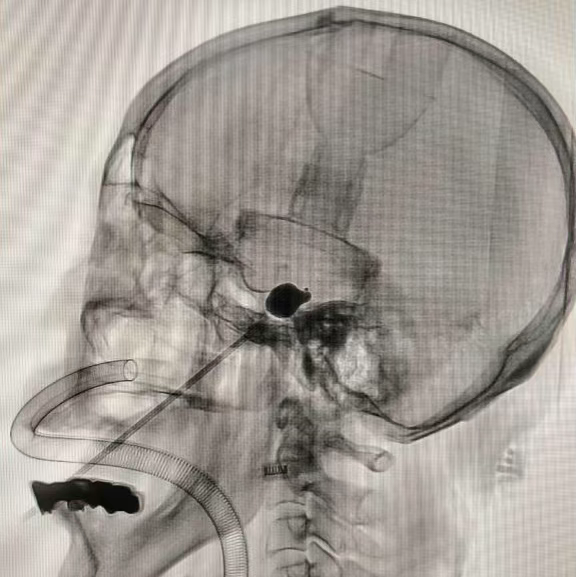

术中操作

与传统手术不同,PBC术如同“精准导航”:无需大切口,仅通过一根纤细导管直达病灶,利用球囊扩张实现治疗目标。